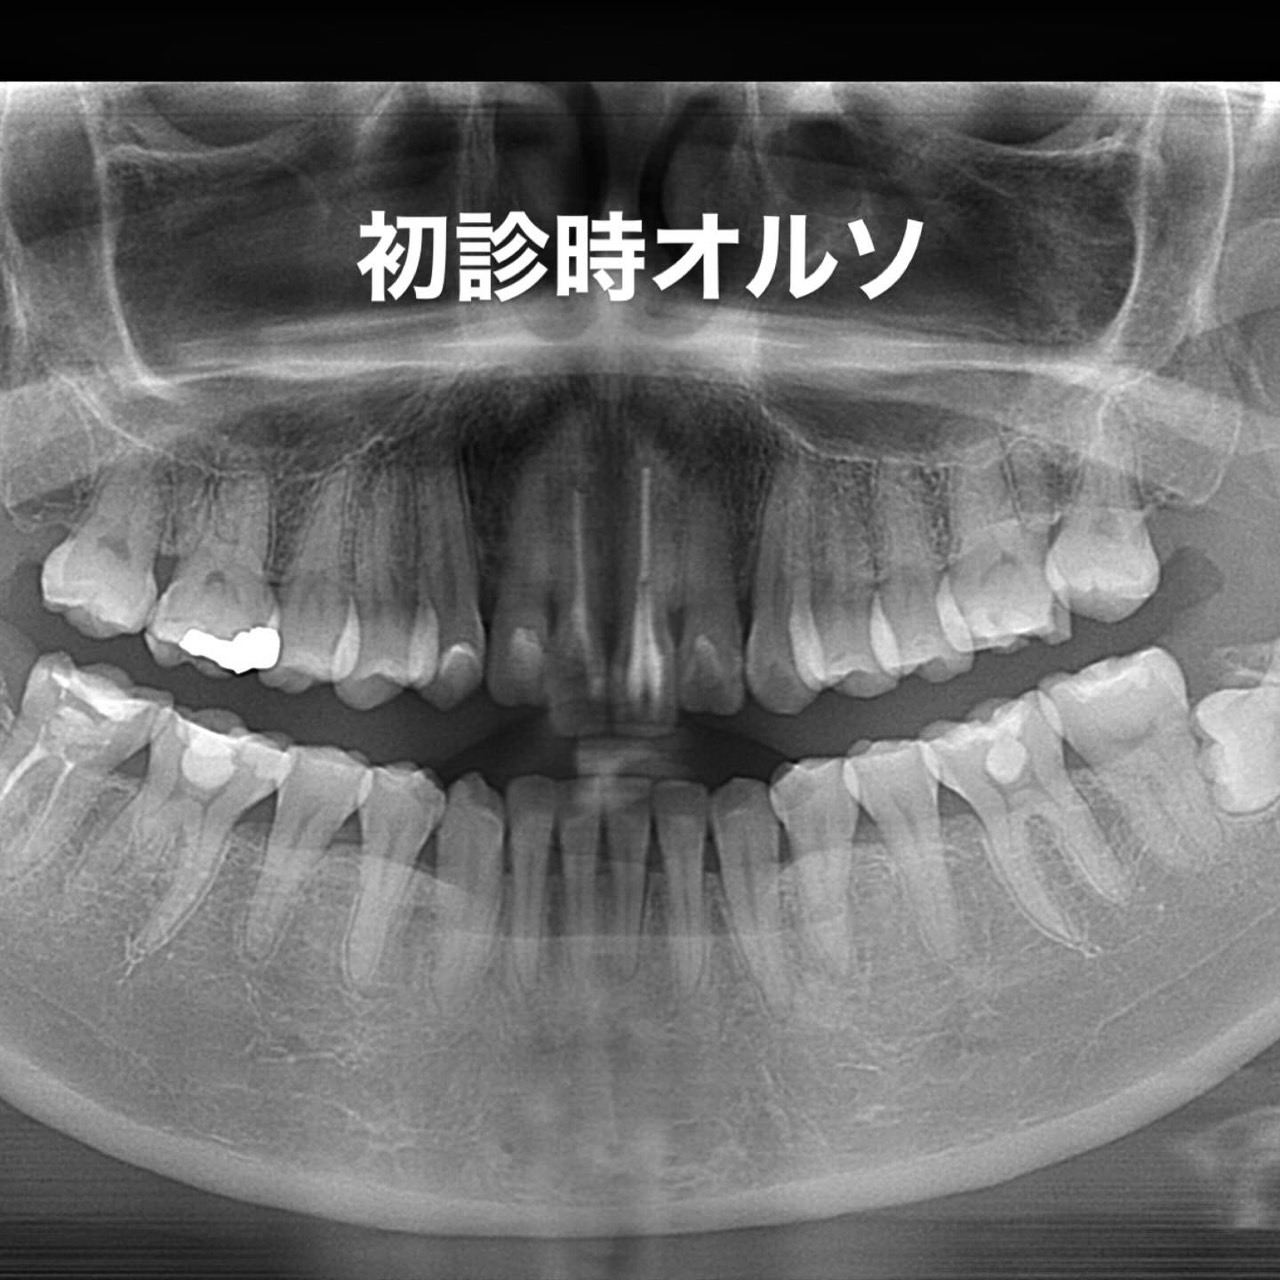

Case023

「歯の長さが短い、歯並びが歪んでる、表面が平面でカッコ悪い、歯茎が腫れている」ということを主訴に来院くださった患者様です。

セラミック矯正は歯科医の技術、センスで仕上がりが全く違うため、審美歯科の中でも担当する歯科医によって最も大きな差の出る診療です。

また、歯並びだけではなく顔貌(お顔立ち)まで綺麗にすることができる診療です。

歯茎の腫れは綺麗に歯を削り直して、正確に型を取り、

精密に作られたセラミックを適合よくセットしてあげることで、前医で入れてから1年以上腫れ続けてた歯茎が1週間で綺麗なピンク色に治りました。

形や並びに関しても、まず歯科医師が「どのような形にするか、どのように並べるか」をイメージしながら綺麗に削ることから始まります。

患者様の主訴通りに綺麗にできて喜んでいただきました。